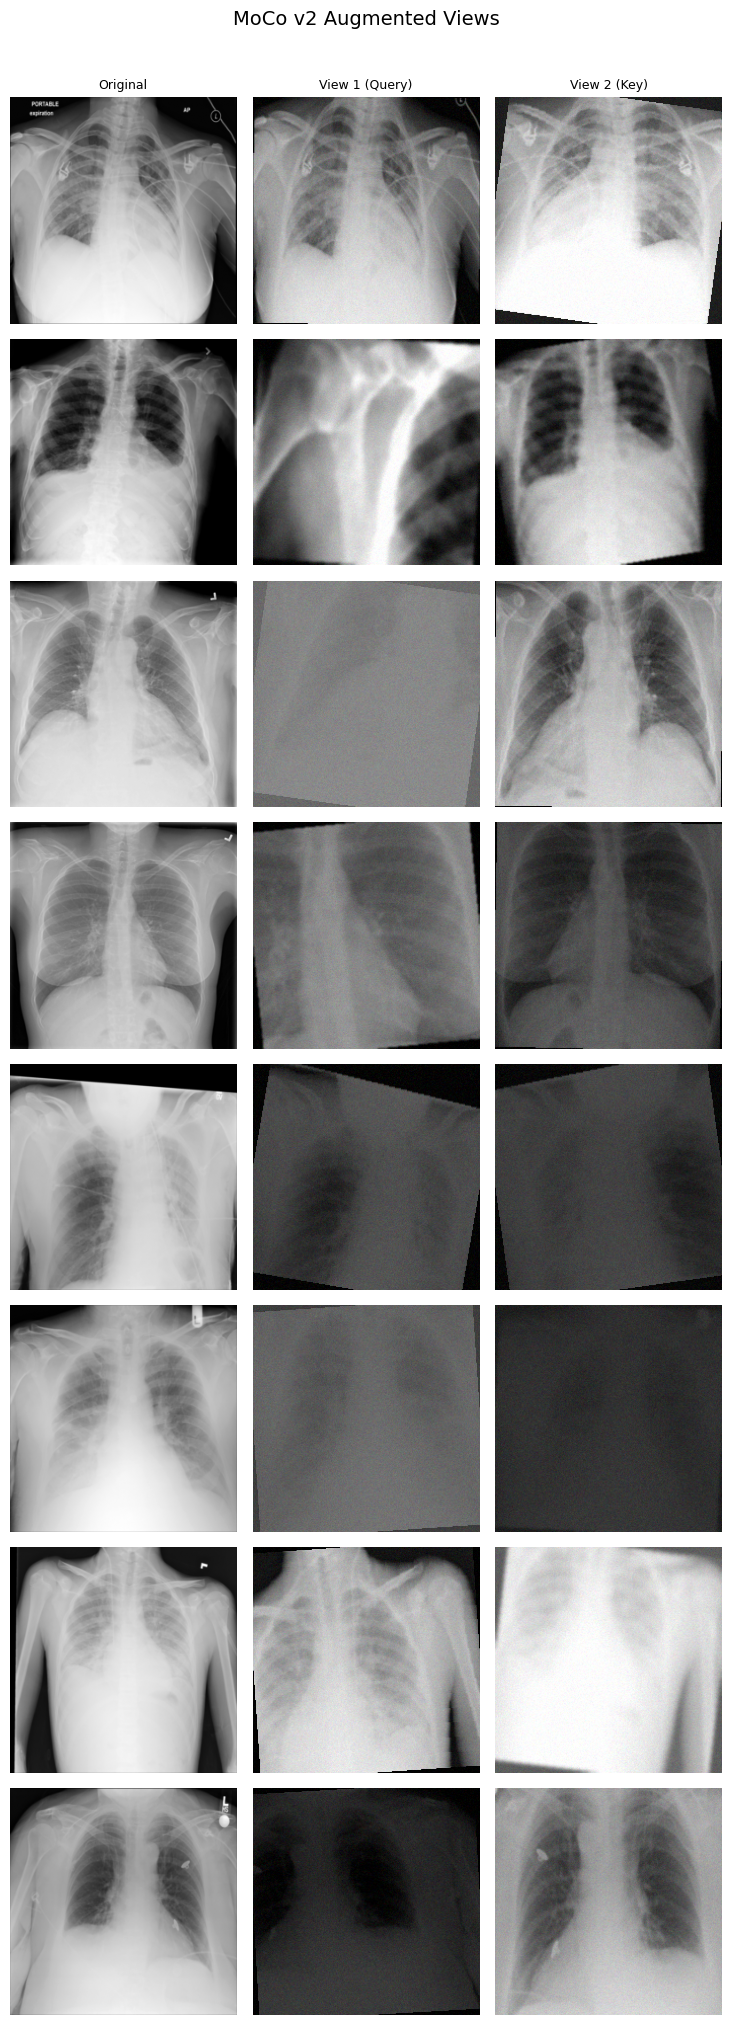

encoder_q and encoder_k.

Each row is one image; the model never sees the

original on the left.Besides, temperature T=0.07 makes the ranking task brutally hard. The model is penalized for not pushing the positive pair to the absolute top of 65,536 entries, so I started the first training run pretty confident the architecture had collapse handled.